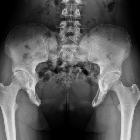

The manta ray sign is a radiographic appearance in bladder exstrophy. It describes wide midline separation of the pubic bones simulating the appearance of a manta ray swimming towards you . The sacrum and iliac wings recall the manta ray’s head and body, with the widely spaced pubic rami forming its cephalic flaps .

- open book pelvic injuries: the smooth arc of the pelvis outline in bladder exstrophy differentiates it from acquired separation of the pubic symphysis seen in open book pelvic injuries